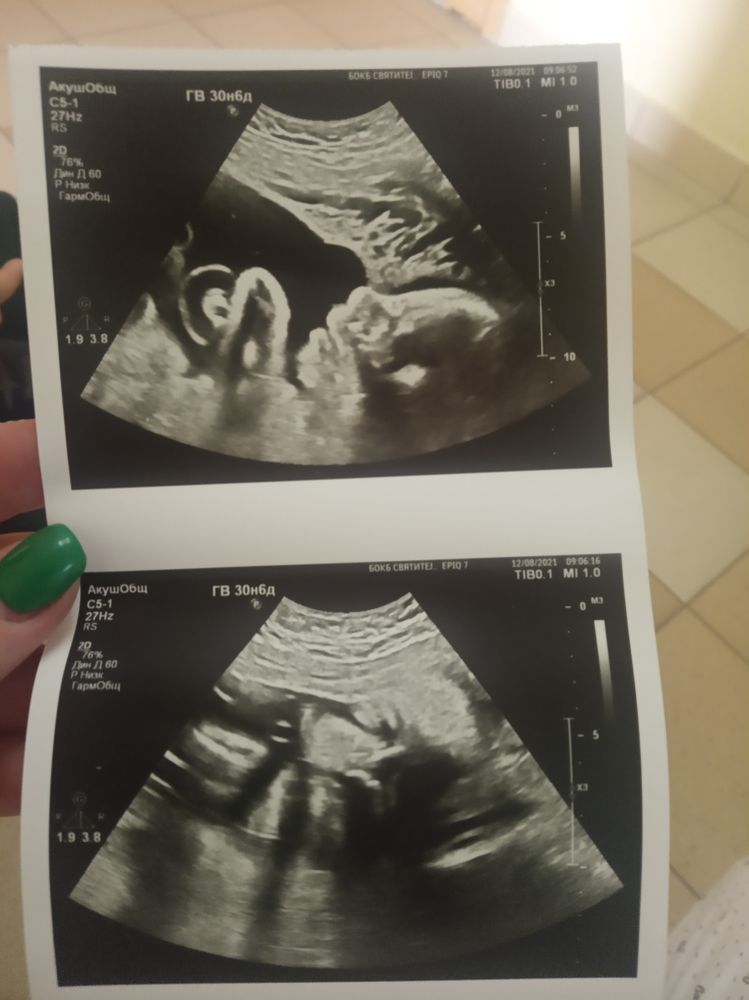

Третий скриниг+фото

Здравствуйте, сегодня показали моего пухлячка🤭 всё у нас хорошо ттт,вес 1900, сказала врач будет крупный, ждём-с встречи 🤗

12.08.2021